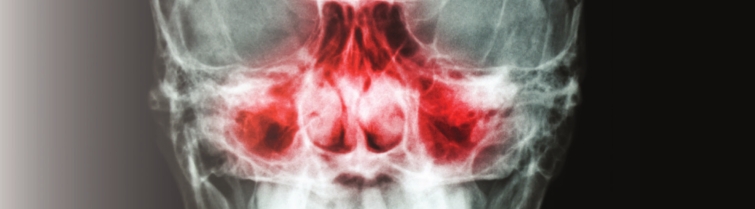

than 30 million Americans suffer from sinus disease, experiencing

symptoms such as facial pain, feeling of fullness in the face,

difficulty breathing through the nose, persistent bad smell in the nose,

postnasal discharge and headaches. How many of these sinus problems can

Ark-La-Tex. “In many cases, sinus disease surrounds the eye and lies up

against the brain,” says Dr. Bill Parker. “This system allows the

surgeon to work more thoroughly and closer to the edge of the senses to

remove as much of the diseased tissue as possible. Also, the Fiagon

System reduces time for certain sinus procedures by as much as 25

percent.